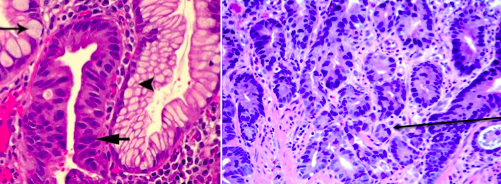

What is the difference b/t these 2 images?

What is the difference b/t these 2 images? Arrow?

Describe the dysplasia in these two esophageal biopsies. How are they different?